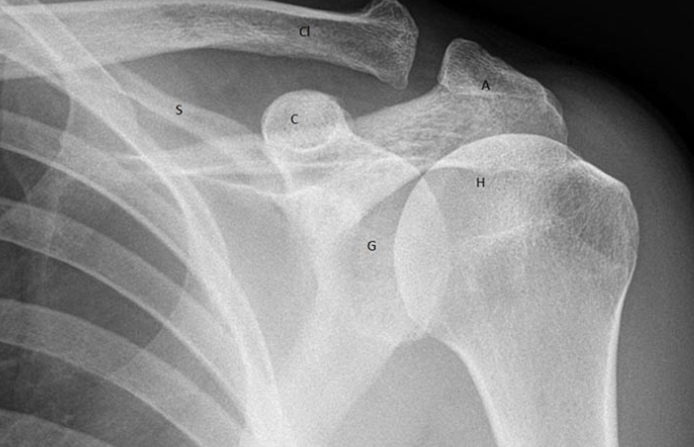

견갑골은 등 상부에 위치한 삼각형 모양으로 상완골을 쇄골과 흉벽에 연결하는 역할을 합니다. 어깨의 움직임에서 가장 중요한 역할을 하는 부분이기도 합니다.

1.3. 견갑골 부상

견갑골 통증 원인 - 충돌, 낙상, 작업 중 골절, 스포츠 및 일상 활동으로 인한 어깨 부상을 입은 사람들도 치유 후 통증이 재발할 수 있습니다. 그 이유는 환자가 몸을 관리하고 돌보는 데 신경을 쓰지 않고, 너무 힘들게 일하고, 무거운 물건을 들거나, 과식을 하고, 초기에 견갑골의 쇠약과 통증을 유발하기 때문입니다.

견갑골 통증 원인 - 견갑골 통증은 경추 손상과 관련이 있을 수 있습니다. 일반적으로 추간판 탈출증, 경추증, 선천적 추간판 붕괴등 접합부에서 경추 손상은 척수 신경을 압박하고 이 신경의 신경 분포에 따라 통증을 자극합니다.